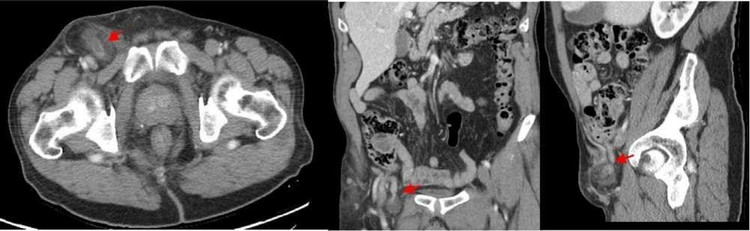

Siêu âm đầu dò tần số cao (5-12 MHz) cho thấy một khối dạng nang hình ống đường kính 0,8 cm được nhìn thấy thoát vị qua khiếm khuyết thành bụng dưới bên phải với một lớp mỡ của mạc nối bên cạnh (hình 1).

thoat-vi-1.jpg

Hình 1